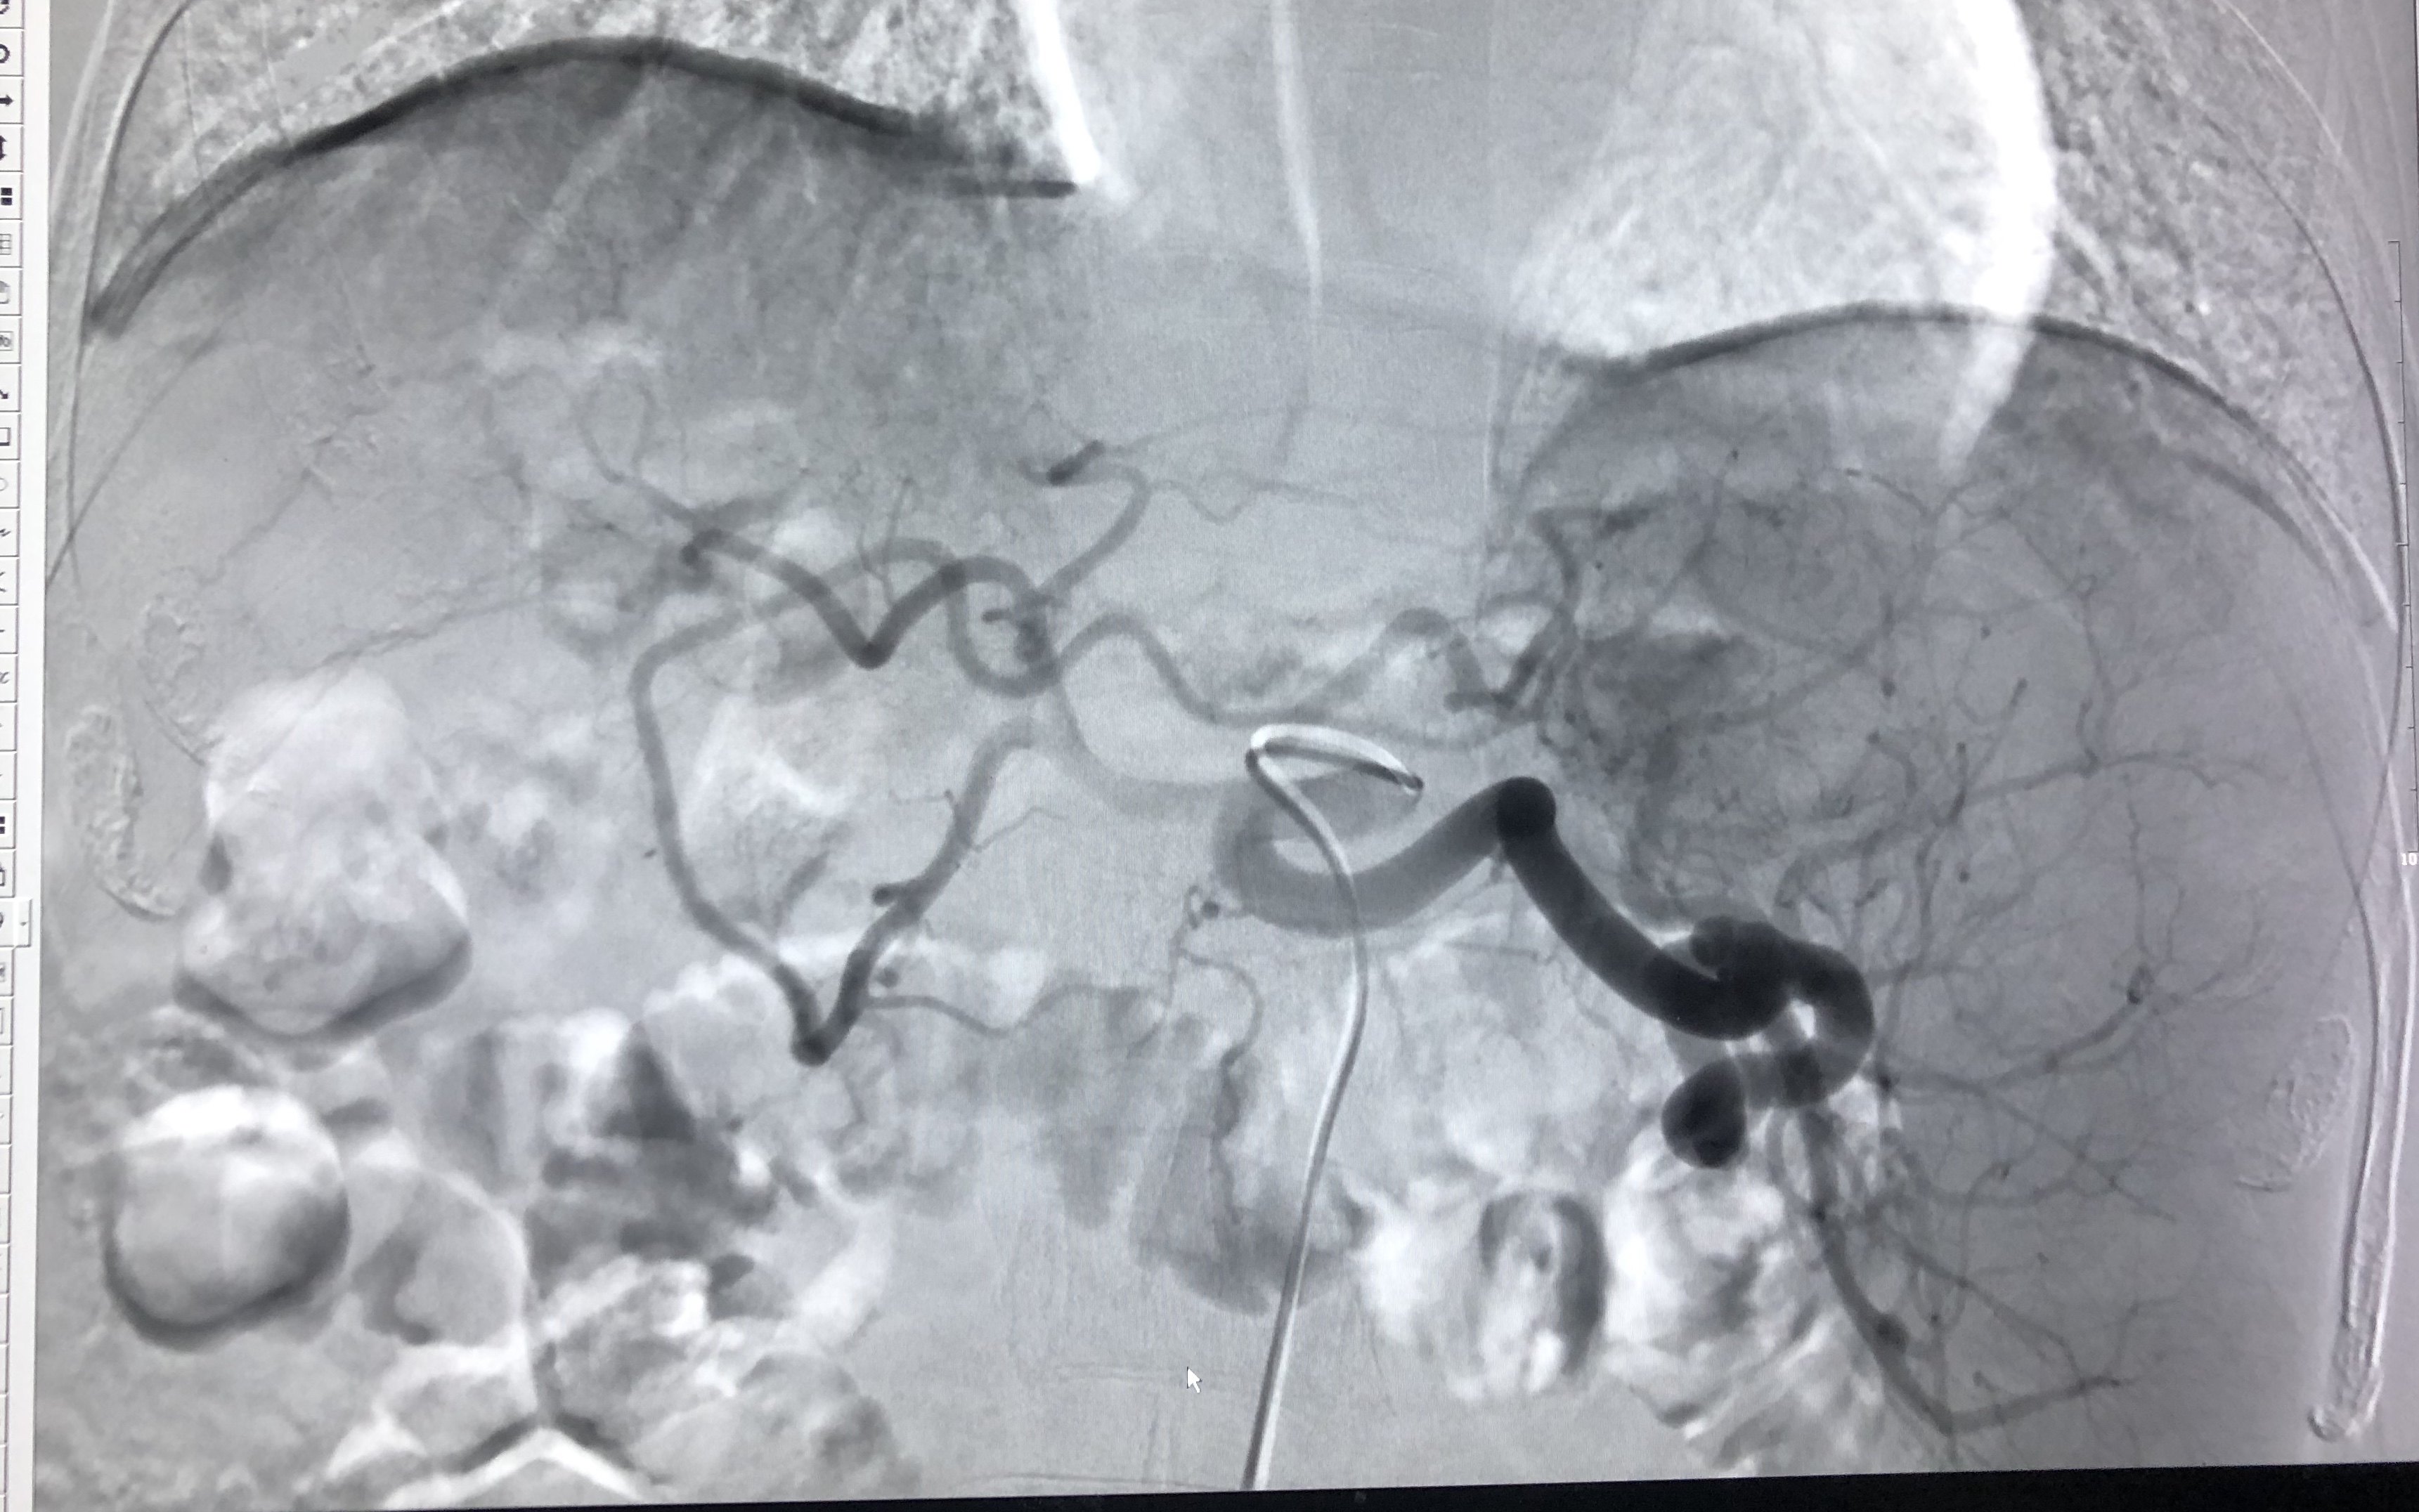

同时行tace术,注射碘化油化疗药乳剂栓塞右肝肿瘤。